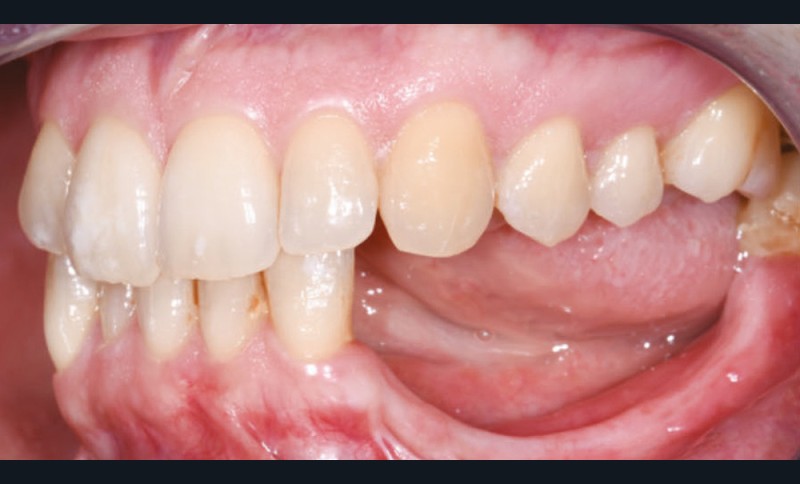

L’examen facial est sans particularités notables. L’examen buccal retrouve un édentement de 33 à 36, compensé par une prothèse amovible, avec une atrophie osseuse transversale et verticale majeure entraînant une augmentation de l’espace prothétique. Il persiste un fin bandeau de gencive kératinisée crestal. Le reste de la denture est sain, l’articulé est en classe I avec un inversé d’articulé sur 13 (fig. 1).